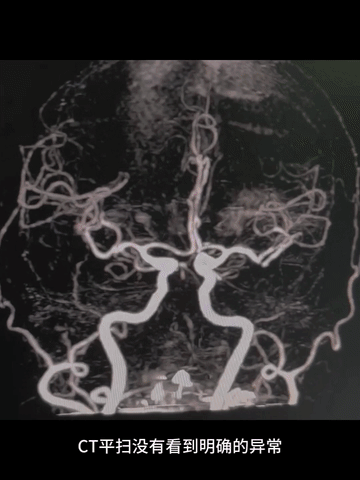

急诊多模式CT

颅脑CT平扫:脑白质改变,余未及其他明确异常。

CTA:基底动脉闭塞,双侧胚胎型后交通,基底动脉尖部可见造影剂充盈;弓上血管迂曲明显,双侧椎动脉V1段均见明显曲折,左侧椎动脉颅内段显影不清,但可见右侧椎动脉颅内段延续至基底动脉闭塞近端。

CTP:脑干和小脑广泛TTP延长,但未见明显CBV和CBF严重降低区域。